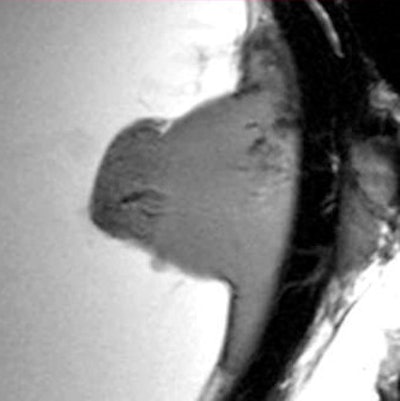

Section enlargement of a T-weighted sagittal image of a malignant uveal melanoma with infiltration of vitreous body, as well as extraocular growth infiltrating the sclera. All images courtesy of the radiology department, University Hospital Greifswald, and pathology department, University Hospital Rostock.